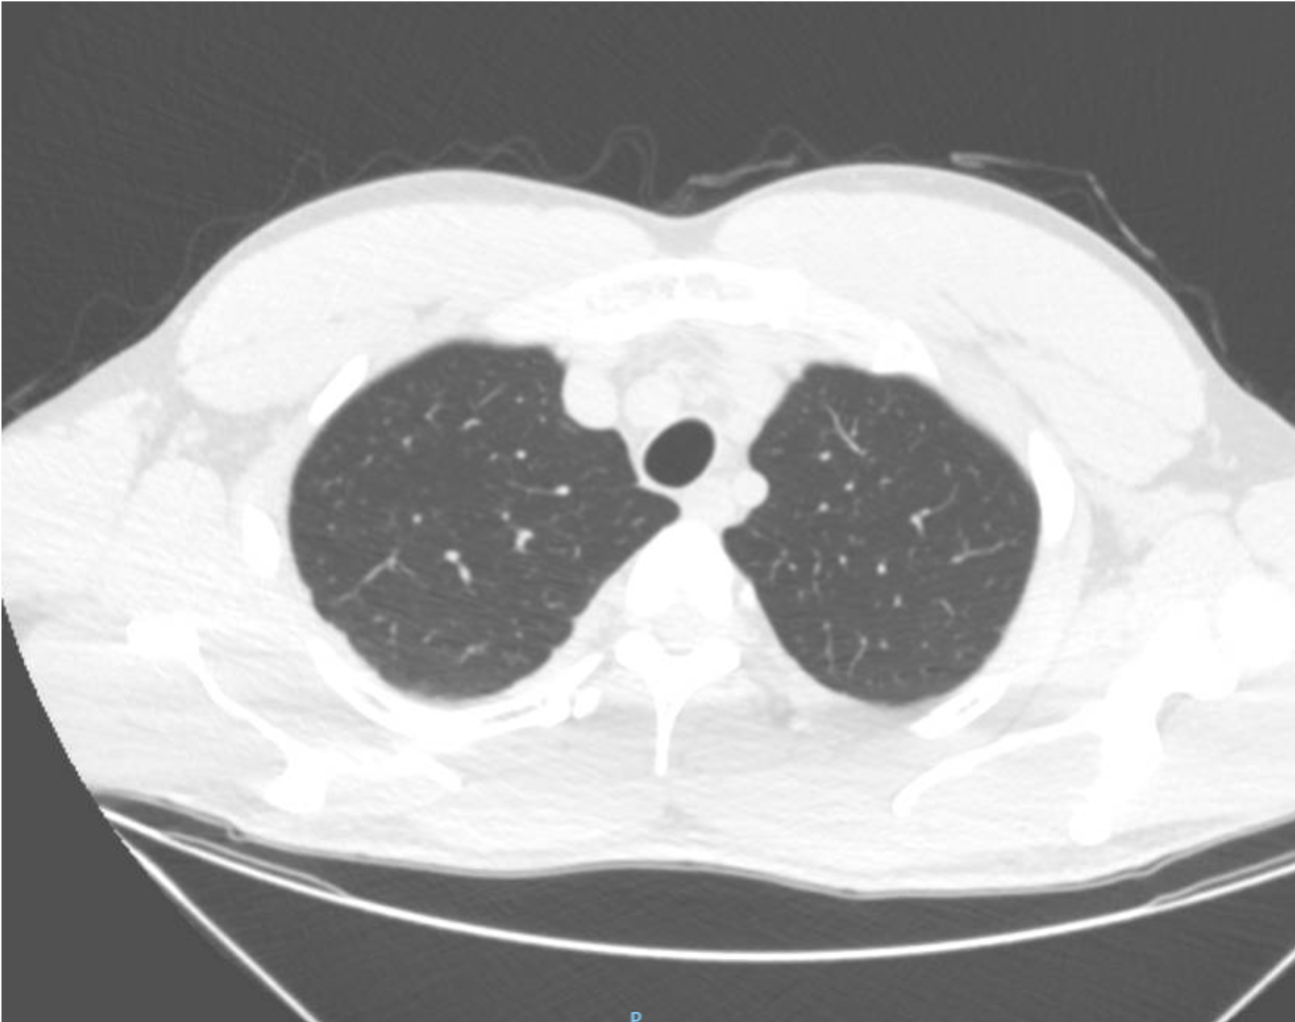

A 30-year-old man presents to the emergency department (ED) due to syncope. For the last 10 days he had had fever, cough and dyspnea. At the ED his peripheral oxygen saturation was 86%, BP 130/80, HR 88bpm, RR 20 /min and his temperature 37.4°C. He was given oxygen via a mask. Chest CT was performed and later lung ultrasound (LUS) was performed in 12 areas longitudinal/oblique views using a convex array probe followed by a linear array probe for details (figure 1).

The patient tested positive for SARS-COV-2. On day 2 after admission the patient’s condition deteriorated, and he was transferred to the ICU. Another chest CT was performed. We show the ultrasound and CT images with corresponding legends (image 1-7 + video 1) and discuss the findings in relation to the diagnostic work-up of COVID-19 pneumonia.

On imaging, initial lesions are usually peripheral because SARS-COV-2 attacks the small distal airways. Several reports have described the findings in chest CT. Most commonly few, small, segmental ground glass opacities are seen peripherally and basal. These may deteriorate to become bilateral and multisegmental and finally consolidation and/or ARDS. Most common LUS signs are: vertical pleurogenic artifacts with varying degree of intensity (from few to confluent). These alternate with clear demarcation to A-lines in the same area, especially in the mid- and upper lung. Pleural thickening, sometimes marked, due to the presence of numerous, small subpleural consolidations. Lobar or translobar consolidations of large size and minimal pleural effusions. The LUS features match with the site and kind on CT.